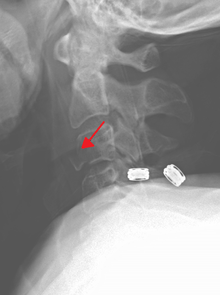

Cervical fracture

A fracture of the base of the dens (a part of C2) as seen on CT. | |

A cervical fracture, commonly called a broken neck, is a catastrophic fracture of any of the seven cervical vertebrae in the neck. Examples of common causes in humans are traffic collisions and diving into shallow water. Abnormal movement of neck bones or pieces of bone can cause a spinal cord injury resulting in loss of sensation, paralysis, or death.

Severe pain will usually be present at the point of injury. Pressure on a nerve may also cause pain from the neck down the shoulders and/or arms. Bruising and swelling may be present at the back of the neck. A neurological exam will be performed to assess for spinal cord injury. X-rays will be ordered to determine the severity and location of the fracture. CT (computed tomography) scans may be ordered to assess for gross abnormalities not visible by regular X-ray. MRI (magnetic resonance imaging) tests may be ordered to provide high resolution images of soft tissue and determine whether there has been damage to the spinal cord, although such damage is usually obvious in the conscious patient because of the immediate functional consequences of numbness and paralysis in much of the body.